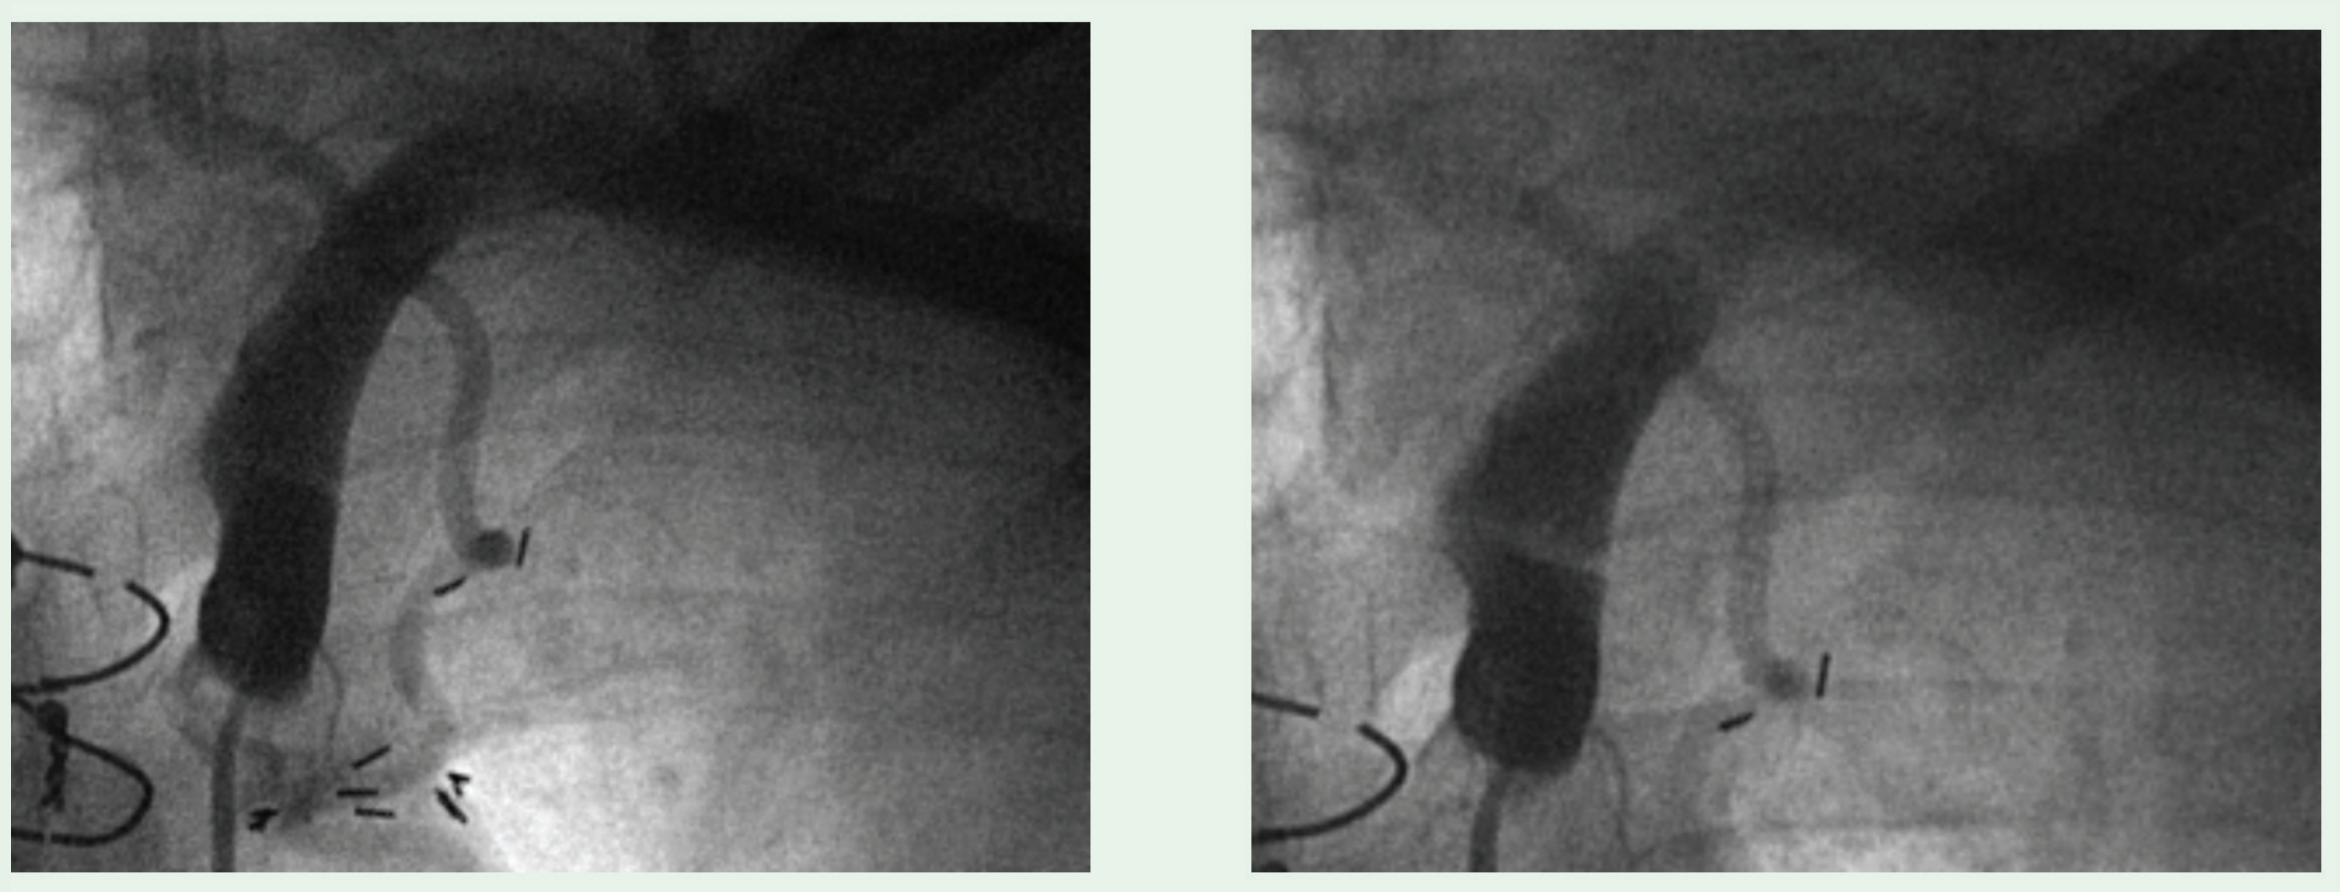

A 74-year-old gentleman with a history of coronary artery bypass grafting using the left internal mammary artery (LIMA) developed recurrent chest pain after a recent coronary intervention. During diagnostic angiography, the left subclavian was engaged with a 6-Fr Judkins 4-right catheter (JR4). Attempts at passage of an 0.035” guidewire were unsuccessful. An angiogram was performed, which demonstrated severe kinking of the proximal ascending portion of the left subclavian artery. Since there was no obvious atherosclerotic disease of the artery it was thought unlikely to represent a true stenosis. The patient was asked to take a deep breath and during inspiration, the guidewire was advanced without difficulty.

A 63-year-old woman with a history of CABG with the use of the LIMA developed recurrent angina with abnormal myocardial imaging and was referred for coronary artery angiography. To engage the left subclavian artery, a JR4 catheter was used to engage the ostium of the left subclavian. Initial attempts at passing an 0.035" J-tipped guidewire into the left subclavian were unsuccessful with resistance met in the proximal ascending portion of the artery. The patient was asked to take a deep inspiration. During inspiration, the guidewire easily crossed the area of resistance and the catheter was advanced.

We describe two cases of patients who had dynamic ascending left subclavian artery kinking. Angiography was indicated for the evaluation of the LIMA bypass graft in both cases. The folding was initially diagnosed when the guidewire was unable to traverse the proximal (not ostial) left subclavian. Interestingly, although both demonstrated physical obstruction to the guidewire, neither case had a translesional gradient during respirations. This would suggest that the anatomic kinking did not have physiological consequences, and these lesions should not be invasively treated. Aside from the anatomic stenosis without physiological consequence, these cases highlight the forces on the proximal left subclavian artery. This region has previously been thought to be a relatively fixed and immobile arterial segment. The clinical consequences of the forces imparted on this segment following endovascular stent implantation are unknown. There are no reported cases of left subclavian artery stent fracture. However, it is doubtful that this has been adequately evaluated. The restenosis rates for subclavian artery stenting are low, with five year patency usually above 85%,3,4 but the cases of restenosis may be related to the regular forces transmitted to this region.